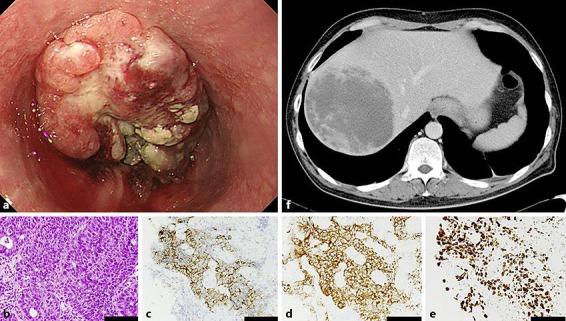

Esophageal large-cell neuroendocrine carcinoma (NEC) is a rare malignant tumor that is characterized by high-grade malignancy and a poor prognosis. However, the rarity of esophageal NEC has prevented the development of an established treatment, and no reports have described a discrepancy in the effectiveness of cisplatin plus irinotecan between primary and metastatic lesions. A 43-year-old Japanese man was referred to our hospital with refractory epigastralgia. A previous gastrointestinal endoscopy had revealed a 50-mm type 2 tumor in the abdominal esophagus. The pathological findings indicated poorly differentiated squamous cell carcinoma. Contrast-enhanced computed tomography revealed a metastatic liver tumor. One cycle of fluorouracil and cisplatin was not effective, and endoscopy was repeatedly performed. The pathological findings indicated a large-cell malignant tumor with tumor cells that were positive for CD56, synaptophysin, and Ki-67 (> 80%). Based on a diagnosis of esophageal large-cell NEC with a metastatic liver tumor, the patient received cisplatin plus irinotecan biweekly. After 4 months, computed tomography revealed marked shrinkage of the metastatic tumor, but the patient complained of dysphagia. Endoscopy revealed enlargement of the primary tumor, which was then treated using radiotherapy plus fluorouracil and cisplatin. The primary tumor subsequently shrank, and the patient's symptoms were relieved, but the metastatic tumor grew. Thus, chemoradiotherapy could be an option for managing a primary esophageal large-cell NEC that does not respond to chemotherapy alone. However, the possibility of an inconsistent response to therapy in primary and metastatic lesions should be considered.

食管大细胞神经内分泌癌(NEC)是一种罕见的恶性肿瘤,其特点是恶性程度高、预后差。然而,食管NEC的罕见性阻碍了既定治疗方法的发展,且尚无报道描述顺铂联合伊立替康在原发性和转移性病变中的疗效差异。一名43岁的日本男性因难治性上腹痛转诊至我院。先前的胃肠内镜检查发现腹部食管有一个50毫米的2型肿瘤。病理结果显示为低分化鳞状细胞癌。增强计算机断层扫描显示有肝转移瘤。氟尿嘧啶和顺铂的一个疗程治疗无效,遂反复进行内镜检查。病理结果显示为大细胞恶性肿瘤,肿瘤细胞CD56、突触素和Ki-67呈阳性(>80%)。基于食管大细胞NEC伴肝转移瘤的诊断,患者接受顺铂联合伊立替康的双周治疗。4个月后,计算机断层扫描显示转移瘤明显缩小,但患者出现吞咽困难。内镜检查显示原发性肿瘤增大,随后采用放疗联合氟尿嘧啶和顺铂进行治疗。原发性肿瘤随后缩小,患者症状缓解,但转移瘤增大。因此,放化疗可能是治疗对单纯化疗无反应的原发性食管大细胞NEC的一种选择。然而,应考虑原发性和转移性病变对治疗反应不一致的可能性。